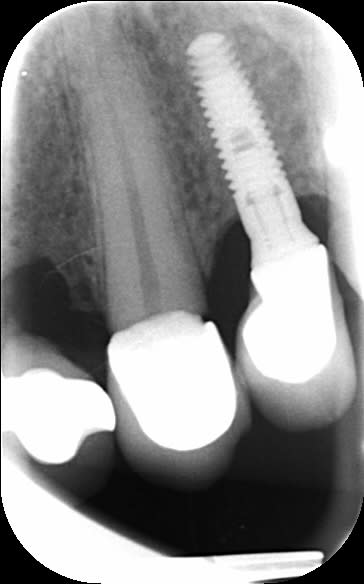

Avant de toucher à quoi que ce soit je cherche la référence de cet implant.

TSV Zimmer

sûr 100%